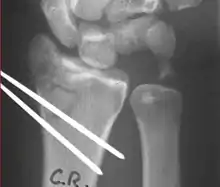

X-rays of pins across a distal radius fracture: Notice the ulnar styloid base fracture, which has not been fixed. This patient has instability of the DRUJ because the TFCC is not in continuity with the ulna.

Treatment options for distal radius fractures include nonoperative management, external fixation, and internal fixation.[4][9] Indications for each depend on a variety of factors such as the patient's age, initial fracture displacement, and metaphyseal and articular alignment, with the ultimate goal to maximize strength and function in the affected upper extremity.[5] Surgeons use these factors combined with radiologic imaging to predict fracture instability, and functional outcome to help decide which approach would be most appropriate. Treatment is often directed to restore normal anatomy to avoid the possibility of malunion, which may cause decreased strength in the hand and wrist.[5] The decision to pursue a specific type of management varies greatly by geography, physician specialty (hand surgeons vs. orthopedic surgeons), and advancements in new technology such as the volar locking plating system.[10]

Surgical options have been shown to be successful in patients with unstable extra-articular or minimal articular distal radius fractures. These options include percutaneous pinning, external fixation, and ORIF using plating. Patients with low functional demand of their wrists can be treated successfully with nonsurgical management; however, in more active and fit patients with fractures that are reducible by closed means, nonbridging external fixation is preferred, as it has less serious complications when compared to other surgical options.[5] The most common complication associated with nonbridging external fixation is pin tract infection, which can be managed with antibiotics and frequent dressing changes, and rarely results in reoperation.[5] The external fixator is placed for 5 to 6 weeks and can be removed in an outpatient setting.[5]